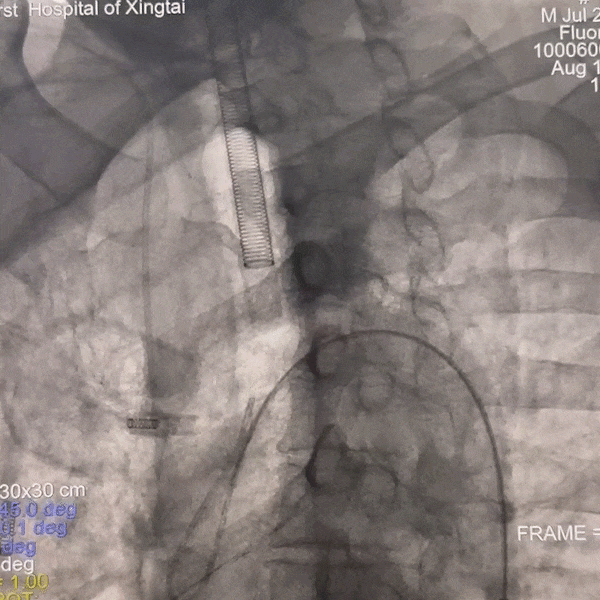

撤出微导丝,沿球囊扩张导管送入4.5*14mm 支架,精确定位后缓慢释放支架。

动脉长鞘怎么置入一技之“长”丨经桡及经股困难入路应用赛诺神畅APEX TRA GC™导引导管建立通路病例合集_https://www.jmylbn.com_新闻资讯_第44张

释放支架

动脉长鞘怎么置入一技之“长”丨经桡及经股困难入路应用赛诺神畅APEX TRA GC™导引导管建立通路病例合集_https://www.jmylbn.com_新闻资讯_第45张

复查正位造影

动脉长鞘怎么置入一技之“长”丨经桡及经股困难入路应用赛诺神畅APEX TRA GC™导引导管建立通路病例合集_https://www.jmylbn.com_新闻资讯_第46张

复查侧位造影